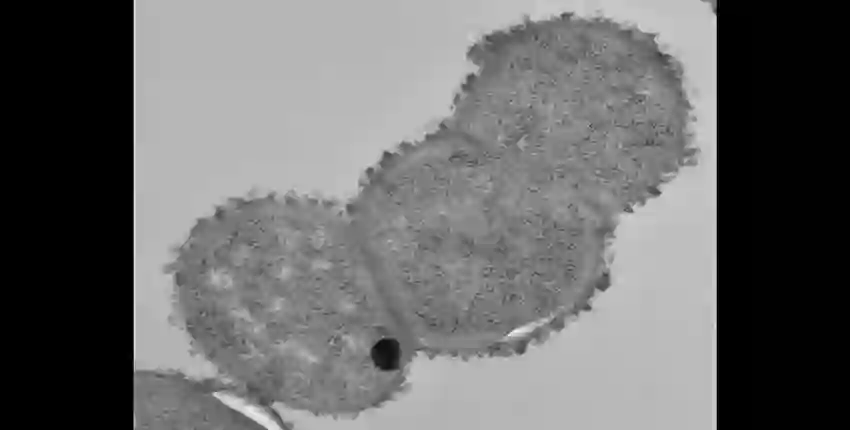

R. gnavus电镜照片

美国麻省总医院(MGH)布罗德研究所(Broad Institute)和哈佛医学院(Harvard Medical School)的研究人员现在发现,一种与克罗恩病相关的、名为活泼瘤胃球菌(Ruminococcus gnavus)的细菌会释放某种多糖(或糖分子链),触发免疫反应。